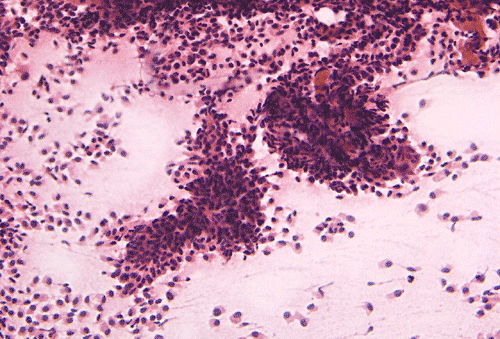

Intraoperative cytologic preparation (Panel C) shows clumps of cells that do not smear out. In between these large clumps are scattered single cells that contain a moderate amount of cytoplasm. On high magnification (Panel D), a papillary pattern is demonstrated in some of the cellular clumps. The nuclei are round to oval, rather monotonous and bland. These cells contain a moderate amount of amphophilic cytoplasm and a well-defined cell membrane.